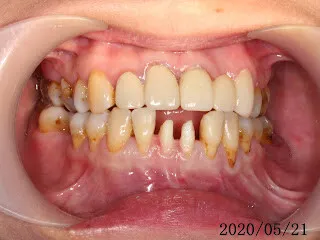

假牙材質2臨床案例...不同的假牙材質+牙齦萎縮